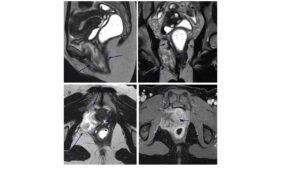

To evaluate pelvic floor integrity and better characterize the lesion’s location, size, and anatomical relationships, MRI with dynamic defecography was requested, partly at the patient’s insistence based on prior advice. MRI showed a well-defined mass measuring 8 × 3 × 4 cm between the anterior rectal wall and the right posterior-inferior vaginal wall, extending into the vulvar region and infiltrating the puborectalis muscle. No nodes or distant disease were identified. The lesion was hyperintense on T2-weighted images with linear hypointense “swirling” areas, consistent with a myxoid matrix. There was no fat suppression on T2 fat-sat sequences. DWI showed high signal without restriction. Post-contrast images demonstrated intense enhancement of fibrous components. The radiologist considered these features highly suggestive of aggressive angiomyxoma (Figure 1), given the myxoid signal, vascular voids, and characteristic pattern of dissecting through pelvic compartments.